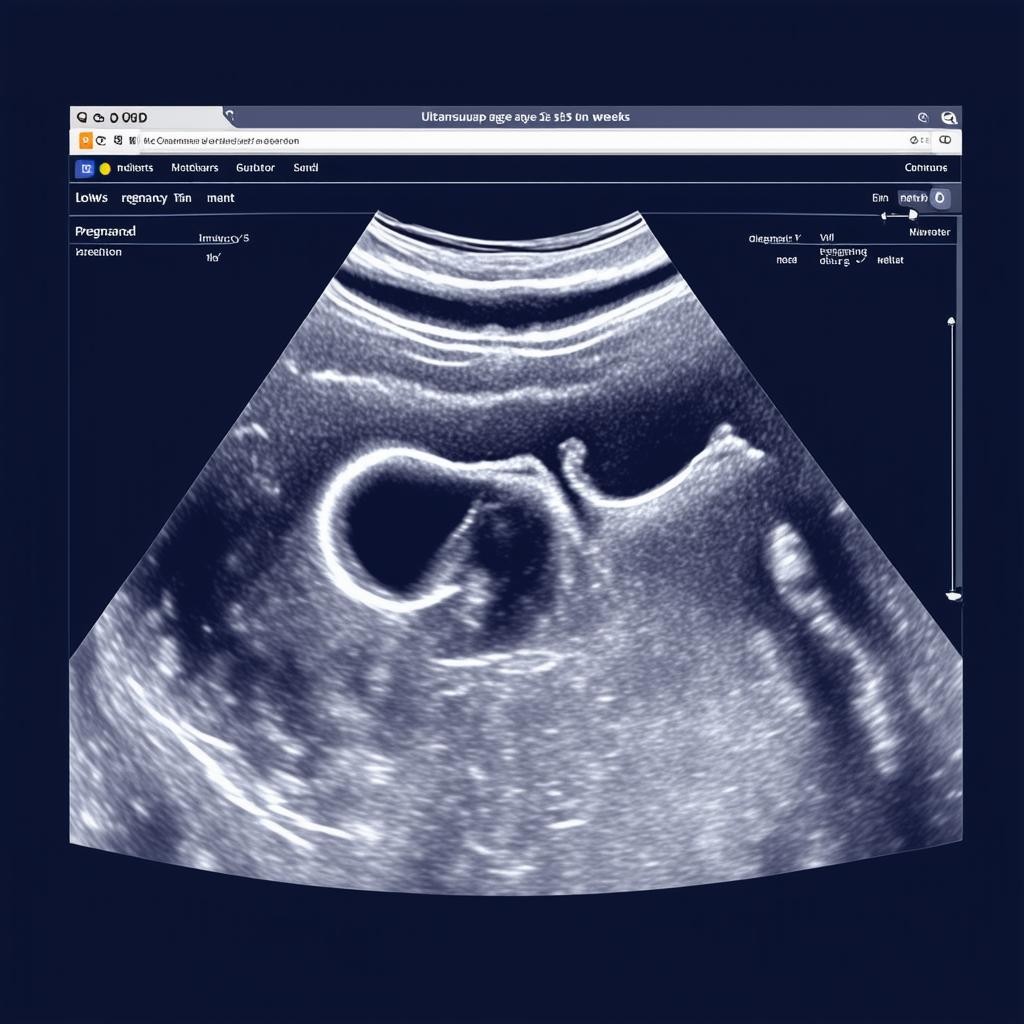

УЗИ на 35 неделе беременности не требует специальной подготовки. Обычно оно проводится трансабдоминально (через живот). Процедура безопасна и безболезненна, длится около 15-20 минут. Врач наносит гель на живот и с помощью датчика получает изображение плода на экране.